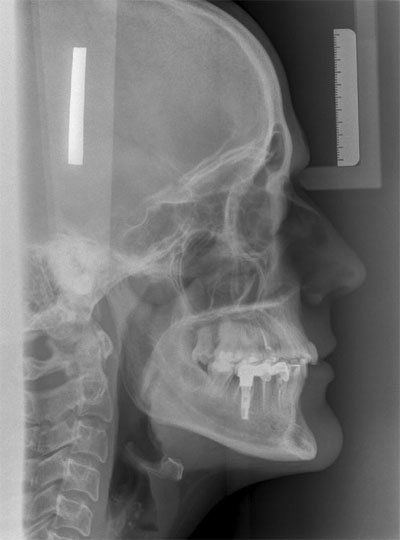

TELERRADIOGRAFÍA LATERAL DE CRÁNEO

Es una prueba diagnóstica donde se estudia el crecimiento facial del paciente en un tratamiento de ortodoncia. Este tipo de pruebas radiológicas conocidas también como cefalometrías son muy útiles en el estudio de ortodoncia, ya que con ellas es posible medir los ángulos y proporciones de los huesos de la cara del paciente y así conocer la relación entre sus estructuras faciales.